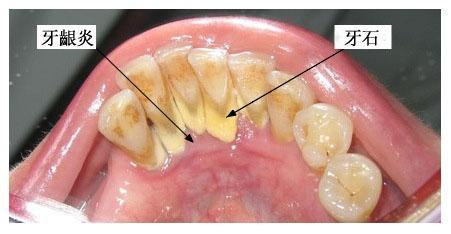

牙齦炎是一種最常見的牙齦疾病,多為牙菌斑引起的牙齦軟組織的非特異性炎癥。

牙齦炎是牙菌斑和牙結(jié)石引起的慢性炎癥,發(fā)炎的時(shí)候吃甲硝唑和頭孢。平時(shí)多喝貝齒寧茶,消菌殺毒,早晚刷牙。使牙齒縫間和齒齦之間的牙刷清洗不到的地方清理干凈,保持口腔內(nèi)的酸堿平衡 堅(jiān)持使用2-3周后刷牙出血癥狀會(huì)停止,腫痛不再。炎癥消退后,去牙醫(yī)診所去洗牙,把牙結(jié)石徹底清理,平日再堅(jiān)持口腔護(hù)理,就可以沒有口臭,炎癥消退,牙齦不腫痛,刷牙不出血了。平時(shí)護(hù)理: